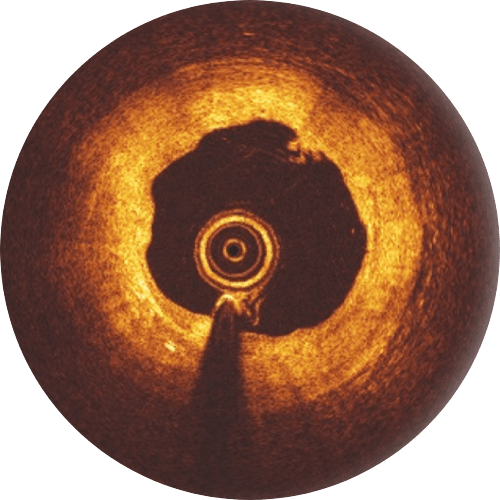

6-month follow-up

While the Magnesium resorption process continues, endothelialization progresses.